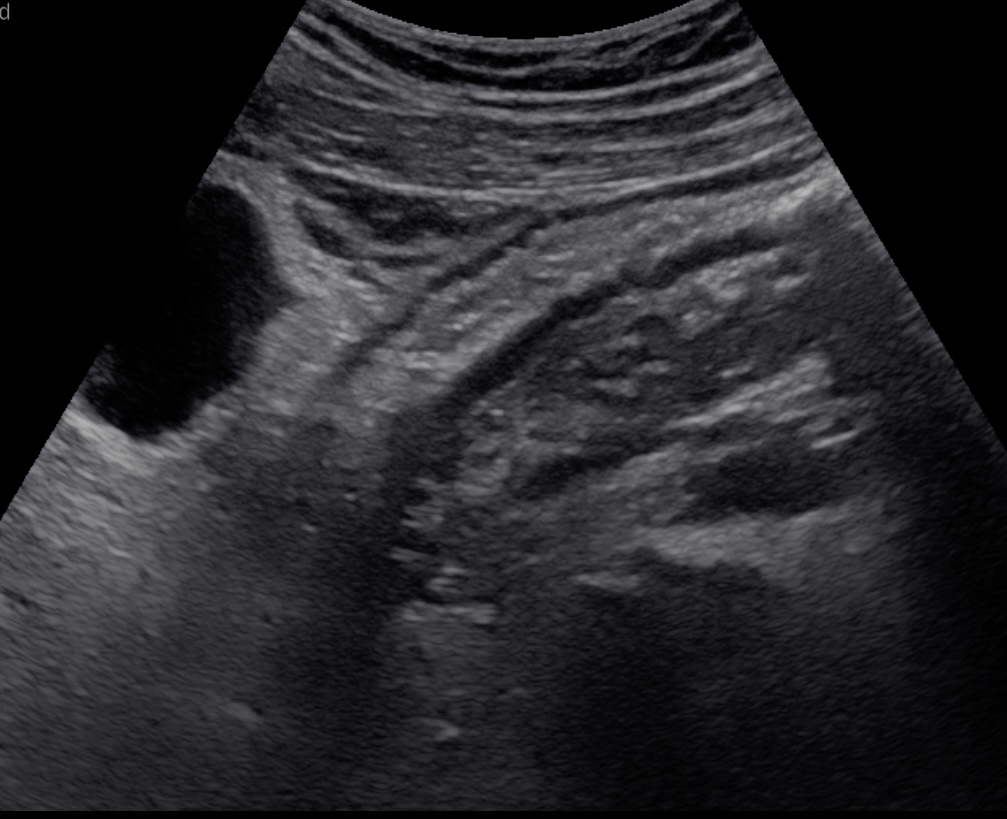

En basse fréquence la musculeuse épaissie hypoéchogène souligne les parois du sigmoide

Epaississement musculeuse et image diverticulaire

Musculeuse sigmoidienne épaissie paroi non inflammée